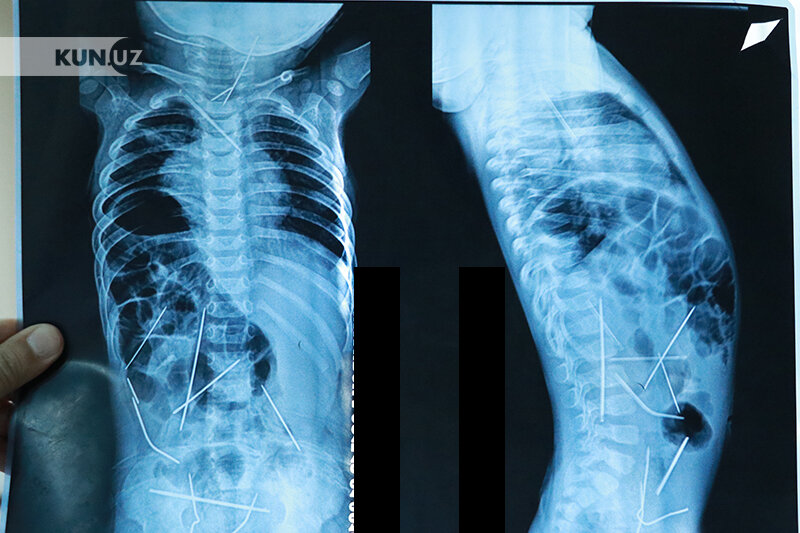

Шу йилнинг январь ойида 11 ойлик чақалоқнинг танасидан 16 дона игна топилгани ҳақида шов-шувли хабарлар тарқалган эди.

Ўшанда, Республика шошилинч тиббий ёрдам илмий марказига келтирилган бола тезкорлик билан жарроҳлик столига ётқизилганди. Марказдаги, Болалар жарроҳлик бўлими томонидан барча игналар танада турлича жойлашгани, яъни - чақалоқнинг йўғон ичак қисмида, сийдик қопи, кўкрак қафасида, боланинг бўйин қисмида, умуртқа поғонасида, юрак остида аниқлангач, бўлим мудири, профессор Акилов жарроҳлик амалиёти ўтказишга киришган эди. Жорий йилнинг 17 январь куни чақалоқ операция қилинди. 9 соат давом этган операцияда 10 нафарга яқин шифокор иштирок этди ва боланинг танасидан 11 дона игна чиқариб олинди.